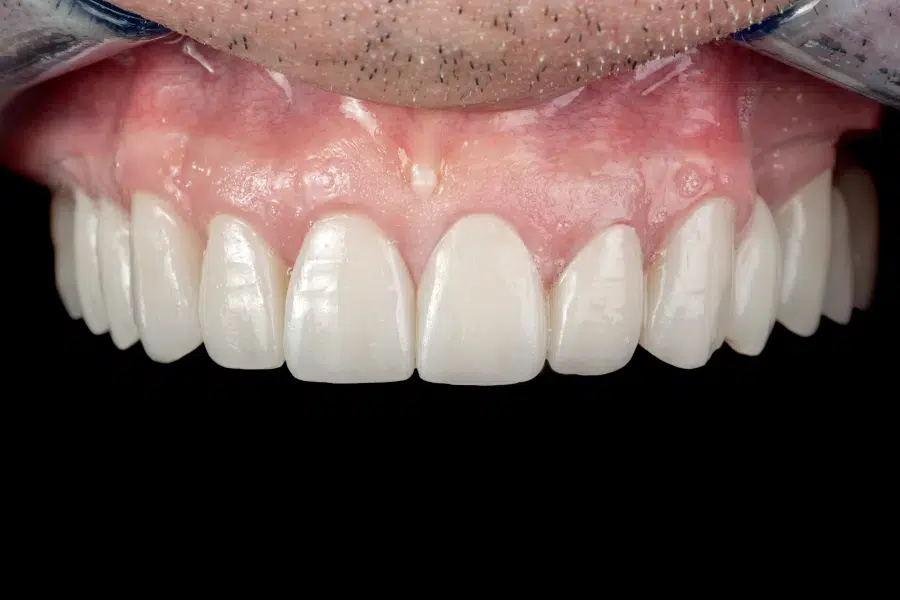

Reabilitare orală completă a maxilarului

Provocarea acestui caz a fost în păstrarea unei forme a noii danturi, cât mai asemănătoare cu a vechii danturi, dând doar un ușor volum noilor coroane, pentru un aspect cât mai natural.

Pacientul și-a dorit o culoare cât mai naturală pentru un aspect de refresh al noii danturi.

Pacientul a beneficiat de coroane și punți de zirconiu și ceramică presată, tratamentul cariilor și tratamente de canal sub microscop.